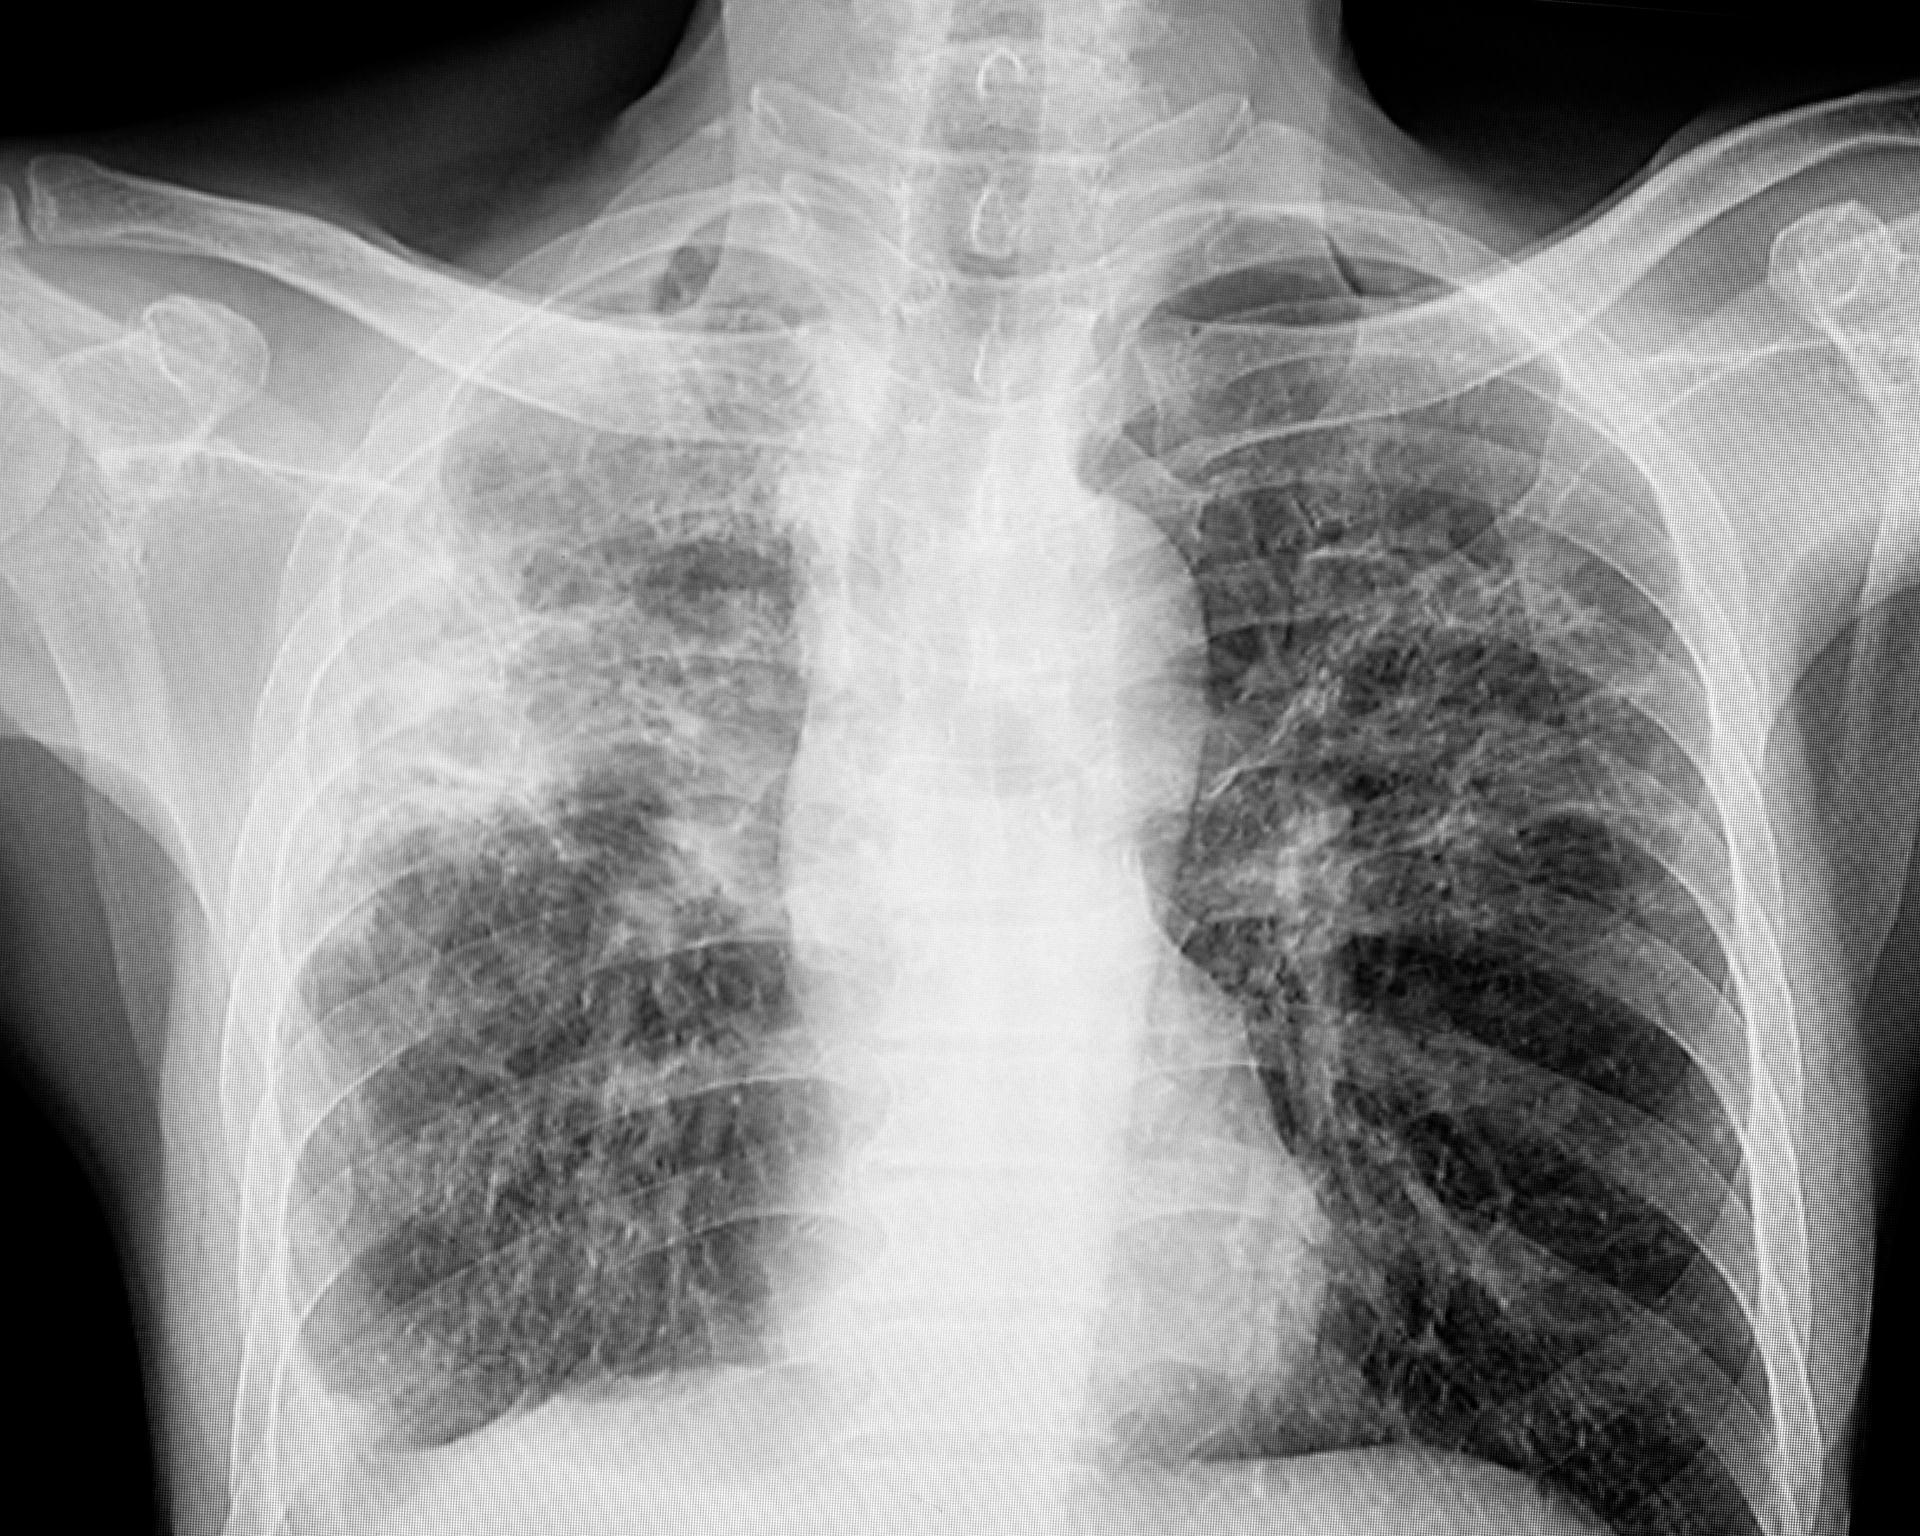

Darker shaded areas on the maps above show higher projected increases in child TB cases (A) and deaths (B) per 100,000 people under the most extreme funding reduction pathway, compared with the historic rates of support. Under this projected funding decrease, the model estimates about 8.9 million additional child TB cases and 1.5 million additional child TB deaths through 2034. Those numbers translate into crowded pediatric wards, more missed school days, and more families facing a disease that is preventable and treatable when health systems are steadily resourced.

The largest projected increases of TB cases cluster in the World Health Organization African and South-East Asia regions. Many of the countries predicted to be hardest hit have a high HIV burden or rely heavily on external funding. When funding drops, TB control can unravel in a predictable sequence: fewer tests and contact tracing, more missed cases, delayed care, and treatment interruptions when clinics face stockouts.